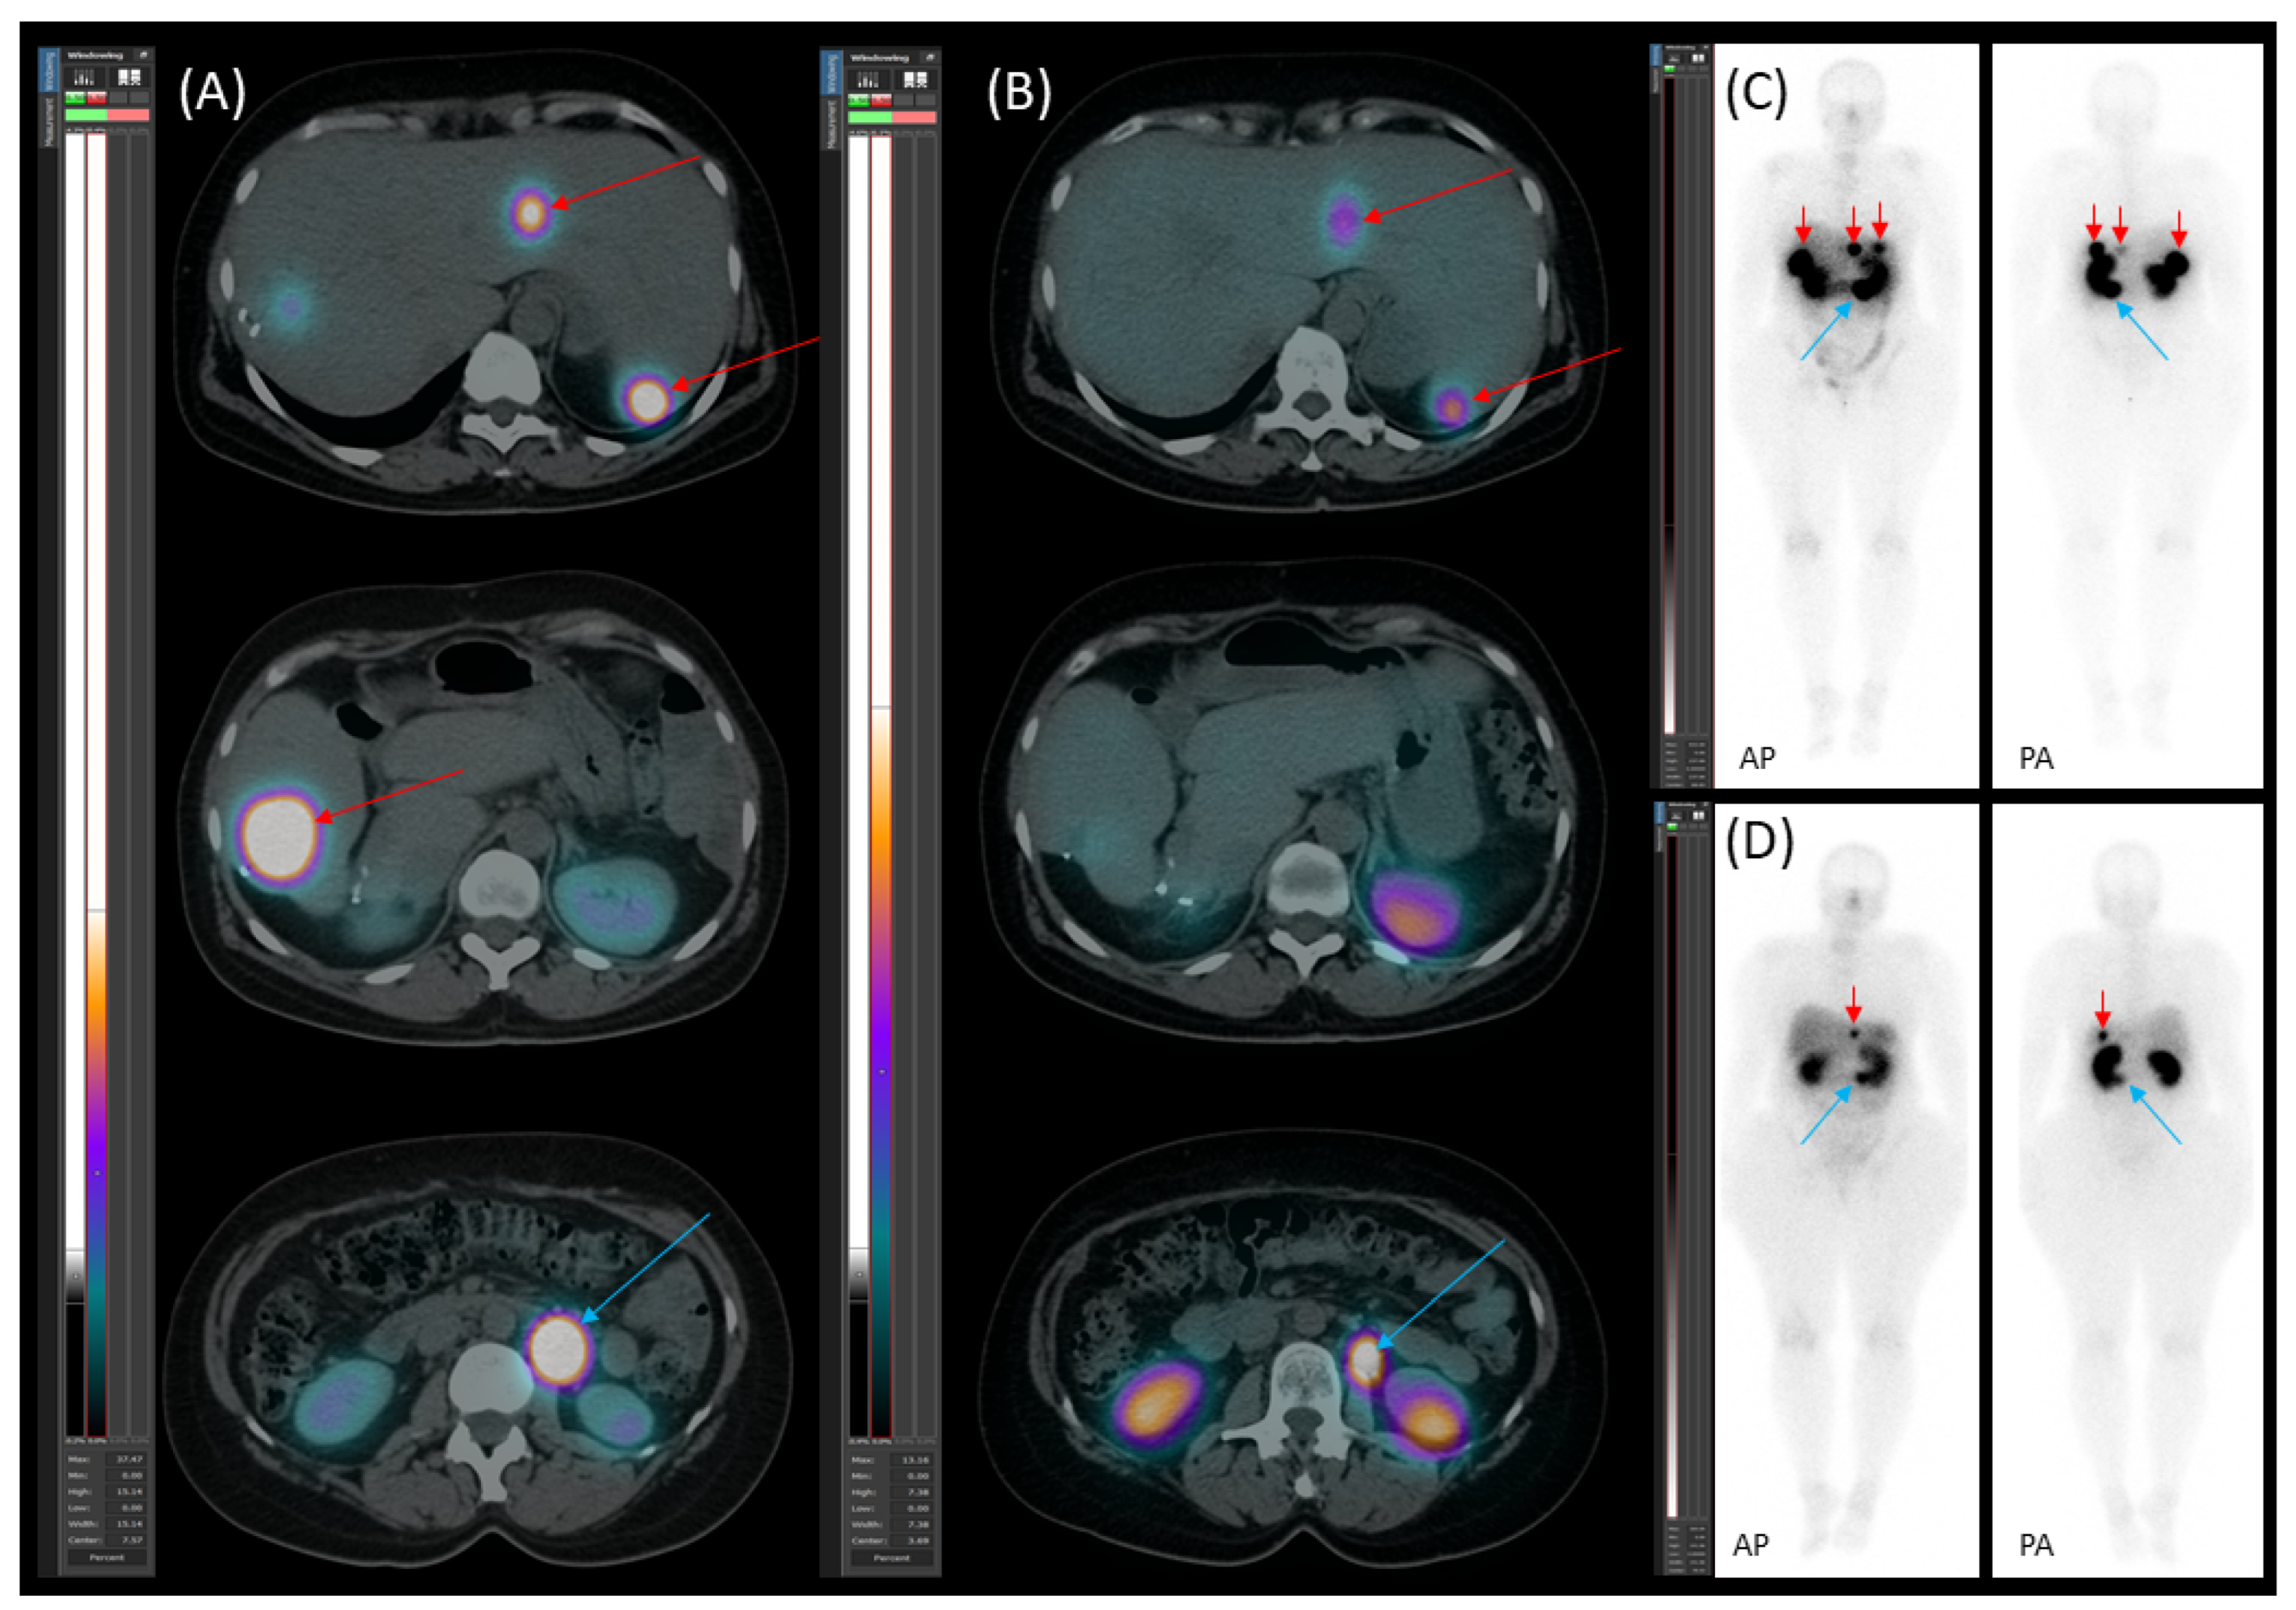

2.2. Preoperative Planning and First-Stage Surgery

2.3. Preoperative Planning and Second-Stage Surgery

2.4. Follow-Up, Disease Progression, and Treatment